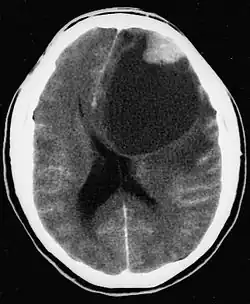

| CT scan of a brain with pleomorphic xanthoastrocytoma. The classic radiographic appearance is one of a superficially situated tumor, here a mural nodule, associated with an underlying cyst. |

- A CT scan of the brain, and/or an MRI scan of the brain and spine, will be performed. A special dye may be injected into a vein before these scans to provide contrast and make tumors easier to see.